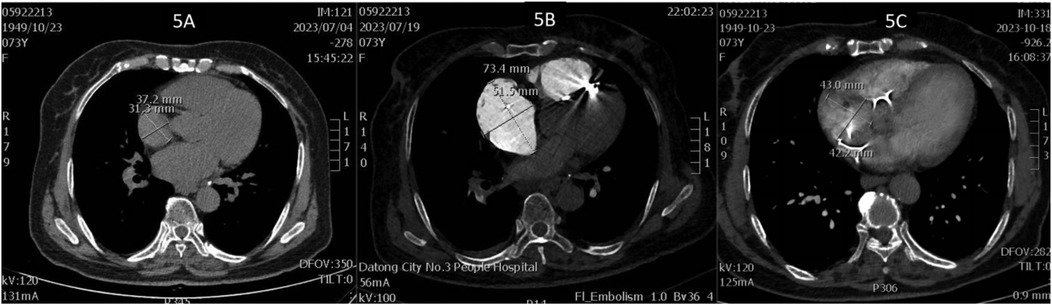

On July 17, a dual-chamber pacemaker (St. Jude Medical PM2172) was implanted via the right subclavian vein under standard parameters: atrial impedance 652 Ω, threshold 1.0 V, P-wave amplitude 10.6 mV; ventricular impedance 768 Ω, threshold 0.5 V, R-wave amplitude 13.6 mV. Strict immobilization of the operative-side upper limb was required within 24 h after surgery. During this period, patients were absolutely prohibited from raising the affected arm above shoulder level and from using the operated-side arm to support themselves when getting out of bed. Additionally, patients were instructed to avoid lying on the surgical side and were encouraged to begin ambulation starting 3 h after surgery. With the day of surgery designated as postoperative day 1 (POD1). By POD2, the incision site remained dry and showed no signs of pocket swelling. At 47 h post-implantation, the patient experienced syncope during ambulation, accompanied by hypotension (76/50 mmHg), tachycardia (110 bpm), tachypnea (30–40/min), and hypoxemia (SpO2 82%). D-dimer surged to 1,617 μg/L. Electrocardiographic findings included VAT (Ventricular pacing, Atrial sensing, and Triggered response) pacing mode with accelerated idioventricular rhythm and atrioventricular dissociation (Figure 2). Device interrogation revealed atrial sensing failure and elevated thresholds, prompting transition to VVI pacing (Table 1). Bedside echocardiography at 18:50 showed: right ventricular enlargement (30 mm), paradoxical motion of the interventricular septum, and moderate pulmonary hypertension (tricuspid peak systolic pressure gradient >60 mmHg). Based on the patient's symptoms, signs, and relevant examinations, the possibility of acute pulmonary embolism was considered high, and immediate treatments were administered, including oxygen inhalation, approximately 800 ml of fluid replacement, and norepinephrine for blood pressure elevation. After the vital signs became slightly stable (blood pressure: 98/60 mmHg, heart rate: 100 beats per minute, respiratory rate: 25 breaths per minute, blood oxygen saturation: 92%), a pulmonary computed tomography angiography (CTA) performed at 22:10 confirmed bilateral pulmonary artery emboli (Figure 3). The patient was transferred to the ICU at 22:30. Alteplase (50 mg) thrombolysis initiated at 23:17 (POD3) yielded rapid symptomatic improvement (SpO2 98% on 5 L/min O2 within two hours). Subsequent low-molecular-weight heparin (5,000 U subcutaneously every 12 h) was administered. By POD3, fresh hemorrhage and pocket distension necessitated intermittent compressive dressing (10 h compression/2 h release for four days, transitioning to 6 h cycles thereafter). On the second day after thrombolysis (POD4), tumor markers were measured in the patient, and the results showed that alpha-fetoprotein (AFP), carcinoembryonic antigen (CEA), carbohydrate antigen 125 (CA125), carbohydrate antigen 15-3 (CA15-3), and squamous cell carcinoma antigen (SCCA) were all within the normal range. The pocket ecchymosis measured approximately 20 cm × 15 cm, but no skin necrosis occurred. No hemorrhage was observed in other organs. Changes in hemoglobin levels are shown in Figure 4. Despite periprocedural ecchymosis, lower extremity ultrasonography on POD8 revealed bilateral calf muscular venous thrombosis. Warfarin anticoagulation commenced on POD9, maintaining an INR of 2–3. The incision healed without complication by POD12. A follow-up echocardiogram on POD8 revealed only a small amount of tricuspid regurgitation. Follow-up evaluations at 28 days and three months post-discharge demonstrated stable pacemaker function (Table 1), resolved pulmonary emboli, and reduced right atrial dimensions (73.4 × 51.5 mm to 43.0 × 42.2 mm; Figure 5). The key time points of the patient are shown in Figure 6.

Figure 5

CT scan images labeled 5A, 5B, and 5C show cross-sections of the chest area. Image 5A displays measurements of 37.2 millimeters by 31.3 millimeters. Image 5B has a highlighted area measuring 73.4 millimeters by 51.5 millimeters. Image 5C shows a region with dimensions of 43.0 millimeters by 42.2 millimeters. The scans show various soft tissues, bones, and potential abnormalities indicated by measurements.

Figure 5. (A) Right atrial diameter upon admission; (B) right atrial diameter 2 h after pulmonary embolism; (C) right atrial diameter 3 months after pulmonary embolism.

This case involves a 73-year-old woman who developed APE with cardiogenic shock 47 h after implantation. Managing it highlights this clinical dilemma. Intravenous alteplase (50 mg) administration achieved rapid symptom resolution within two hours, albeit precipitating pocket hemorrhage and swelling. Intermittent elastic compression bandaging was used (10 h cycles for four days, then transitioning to 6 h intervals). This method effectively mitigated hematoma expansion without causing skin necrosis, which aligns with reported strategies for controlling post-implantation hemorrhage (23). Warfarin was initiated on day seven, with the dosage titrated to maintain an INR of 2–3. Follow-up imaging at three months showed resolved DVT, pulmonary emboli, and right atrial remodeling (from 73.4 × 51.5 mm to 43.0 × 42.2 mm; see Figure 5). These findings underscore the viability of this approach.